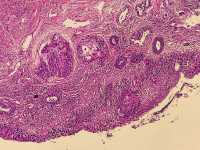

女39岁宫颈活检HPV53HPV58阳性 CIN2?

免疫组化分别是P16 Ki67

考虑为CIN2累腺

HSIL累腺。